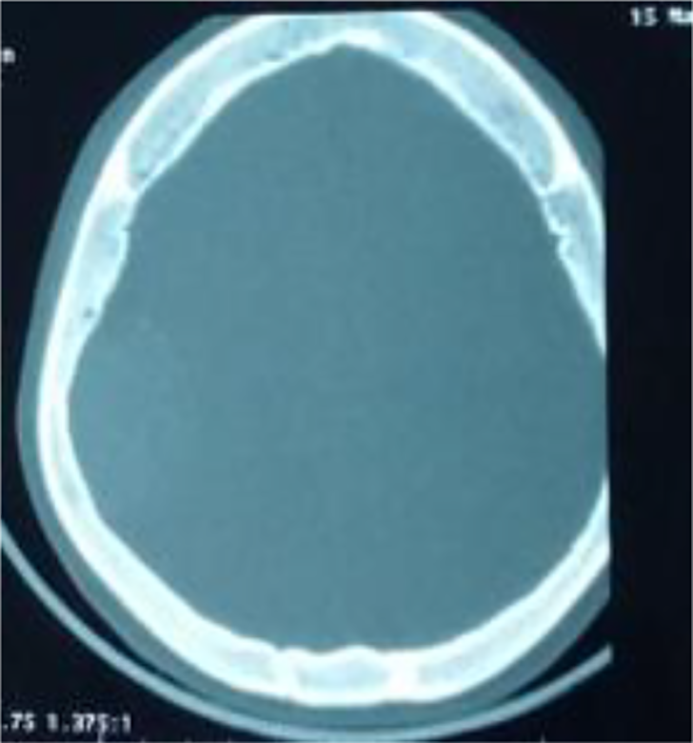

As part of the investigation into his facial oedema and headaches, a cerebral CT scan was carried out two days after his admission to the hospital, showing two extra dural haematomas on the right frontal side measuring 7.1 mm and the right parietal side measuring 27 mm, with no signs of involvement (Fig. 1) or associated bone fracture, and an abnormally thick diploid (Fig. 2).

Fig. 2. Axial scans through a bone window showing thick bone with no visible fracture.